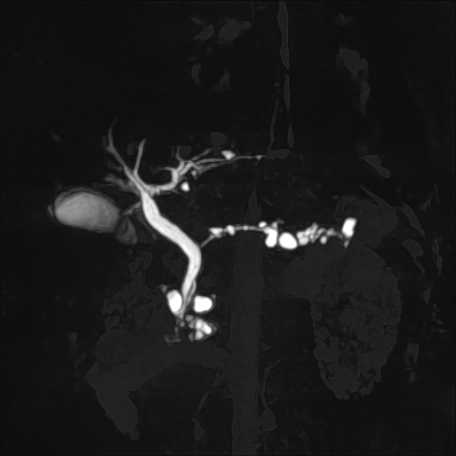

腹部

膵管内乳頭粘液性腫瘍(IPMN)